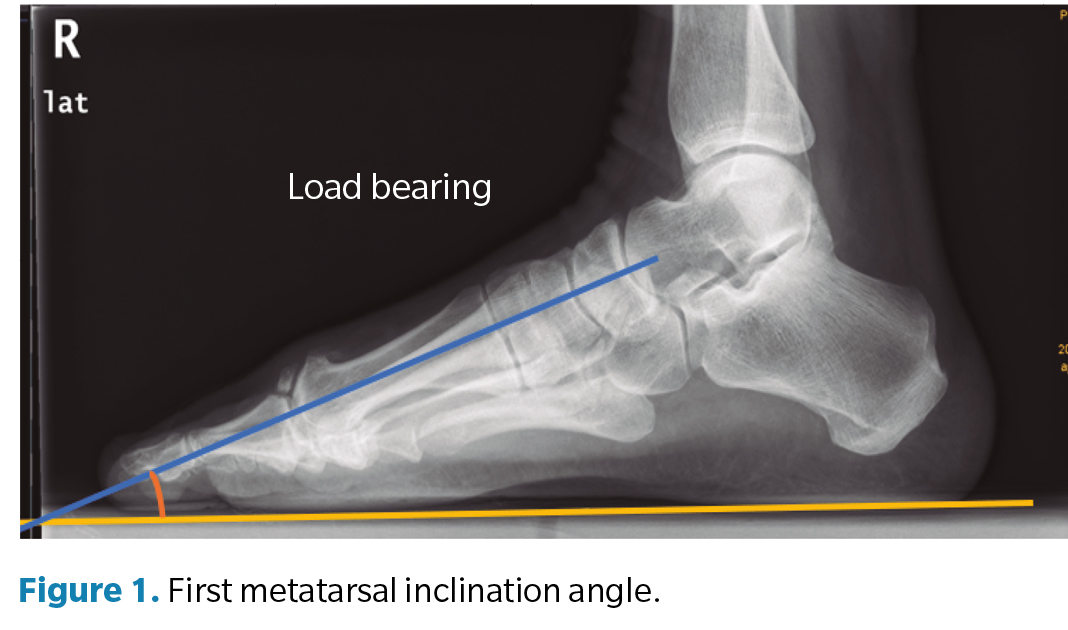

Regarding the goniometric variables in the lateral X-ray, the following angles were obtained: first metatarsal inclination angle, calcaneal inclination angle, Meary-Tomeno line, and internal Costa Bartani angle. The metatarsal inclination angle or Fick angle involves the inclination of the 5 metatarsals; however, for this study, only the inclination angle of the first metatarsal was considered (Figure 1), which was defined by the diaphyseal axis of the first metatarsal with the horizontal plane of the ground support11. The calcaneal inclination angle (Figure 2) is defined by the axis of the calcaneus, a line connecting the calcaneal tuberosity to the plantar margin of the anterior extension of the calcaneus near the calcaneocuboid joint, and the support plane (line formed by the proximal plantar tuberosity of the calcaneus and the head of the 5th metatarsal). A value of 20° is considered normal(12). The Meary-Tomeno line (Figure 3) is defined as the line passing through the axis of the talus (bisector of the angle formed by the tangent to the superior and inferior borders of the talus) and the axis of the diaphysis of the first metatarsal13). The internal Costa Bartani angle (Figure 4) is defined as the union of 3 points: the lowest point of the medial sesamoid, the lowest point of the posterior tuberosity of the calcaneus, and the lowest point of the talonavicular joint(14)..

These angles were chosen because they best represent the alignment of the internal longitudinal arch, in which the decrease or inclination towards the plantar side is associated with flattening of the arch(15).